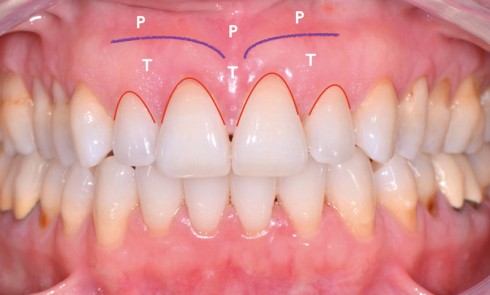

Article réservé à nos abonnés Recouvrement de récessions gingivales de classe III de Miller avec lésions cervicales d’usure – Partie I

Examen cliniqueNotre patiente de 44 ans, soucieuse de son sourire, se plaint d’hypersensibilités dentinaires et désire recouvrir ses racines dénudées....